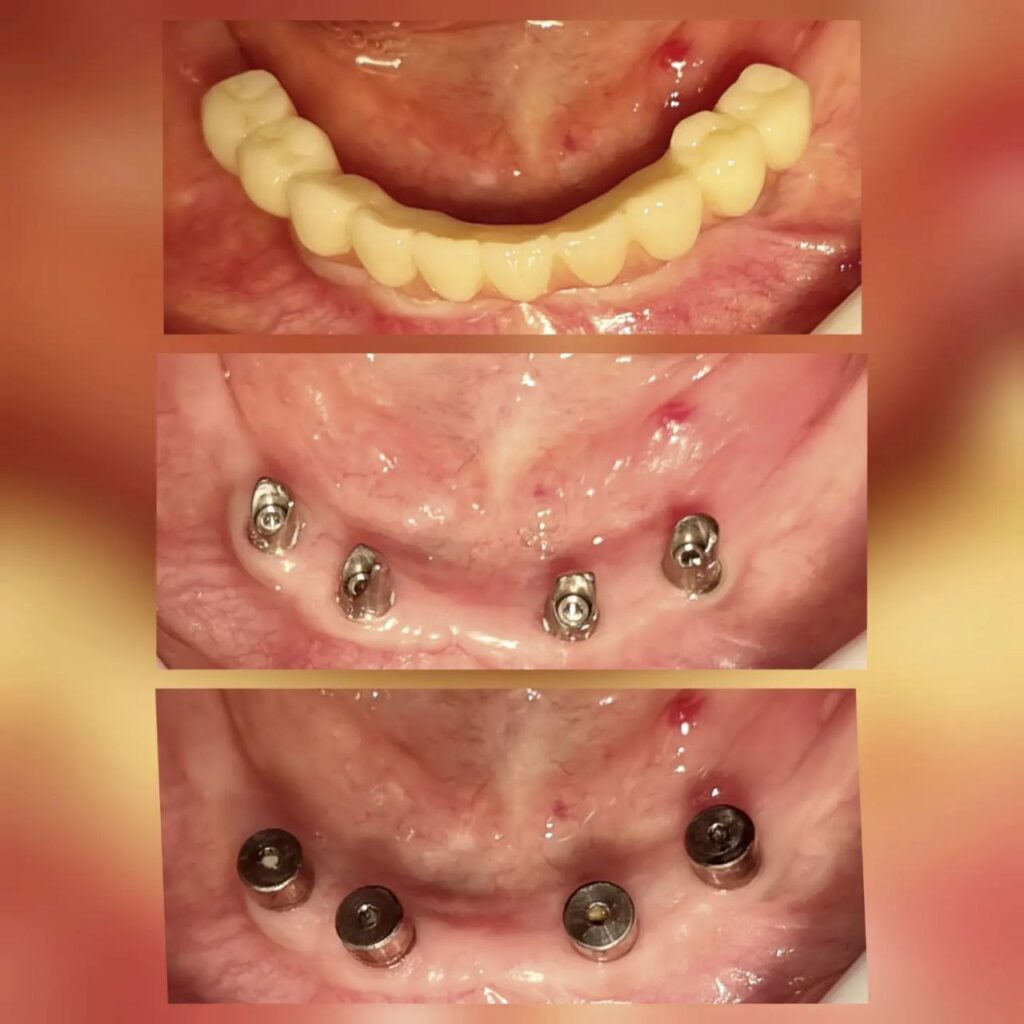

کاشت ایمپلنت دندان

اطمینان حاصل کردن از اینکه دندانهایتان به نحوی زیبا و طبیعی جایگزین شدهاند، از اهمیت بسیاری برخوردار است. ایمپلنت دندان به عنوان یک روش درمانی دائمی در دندانپزشکی شناخته میشود که حاصل آن، یک دندان زیبا و طبیعی در دهان شما خواهد بود.

هرچند که این روش درمانی هزینهی بیشتری نسبت به روشهای دیگر دارد، اما ارزش زیبایی که ایجاد میکند، قابل انکار نیست. ایمپلنتها به قدری شبیه به دندانهای طبیعی هستند که به سختی میتوان آنها را از دیگر دندانها تشخیص داد.